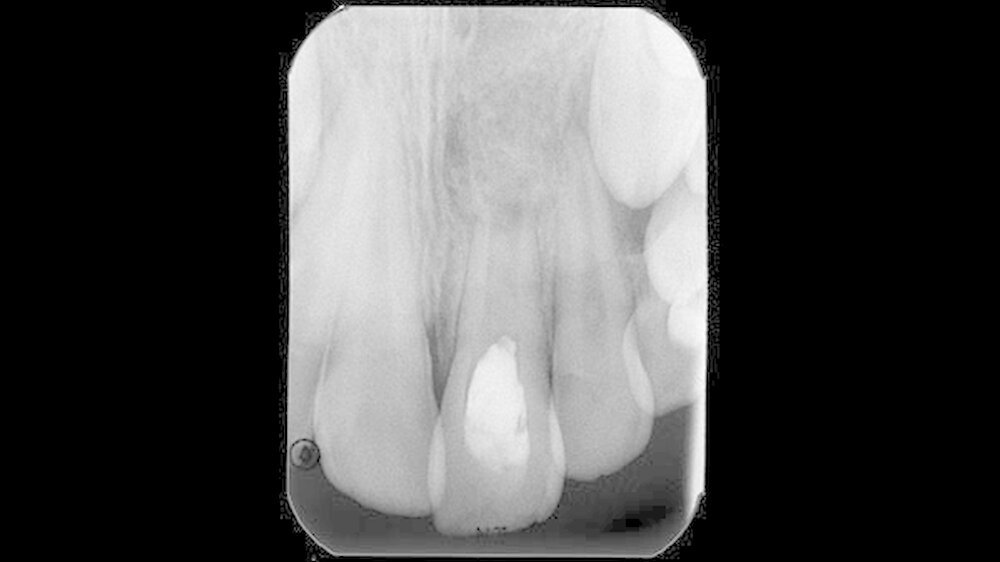

Auch zehn Monate nach Behandlungsübernahme, in denen in einem Abstand von vier bis sechs Wochen Kalziumhydroxideinlagen in den gereinigten Wurzelkanal eingebracht wurden, war der Patient zwar beschwerdefrei, der Wurzelkanal jedoch nicht zu trocknen. Aus diesem Grund wurde eine weitere Zahnfilmaufnahme zur weitergehenden Diagnostik angefertigt (Abbildung 3).

Der Zahnfilm ließ im Vergleich zur Voraufnahme bei Behandlungsübernahme eine Reduktion der apikalen Osteolyse und eine Abnahme der Radiotranslumniszenz erkennen. Dies wurde als fortschreitender Heilungsprozess bei ossärer Regeneration bewertet. Über weitere zwölf Monate erfolgte somit in einem vier- bis sechswöchigen Turnus eine schonende Reinigung und Desinfektion nach dem geschilderten Vorgehen und eine wiederholte Kalziumhydroxideinlage mit abschließendem bakteriendichten Verschluss.